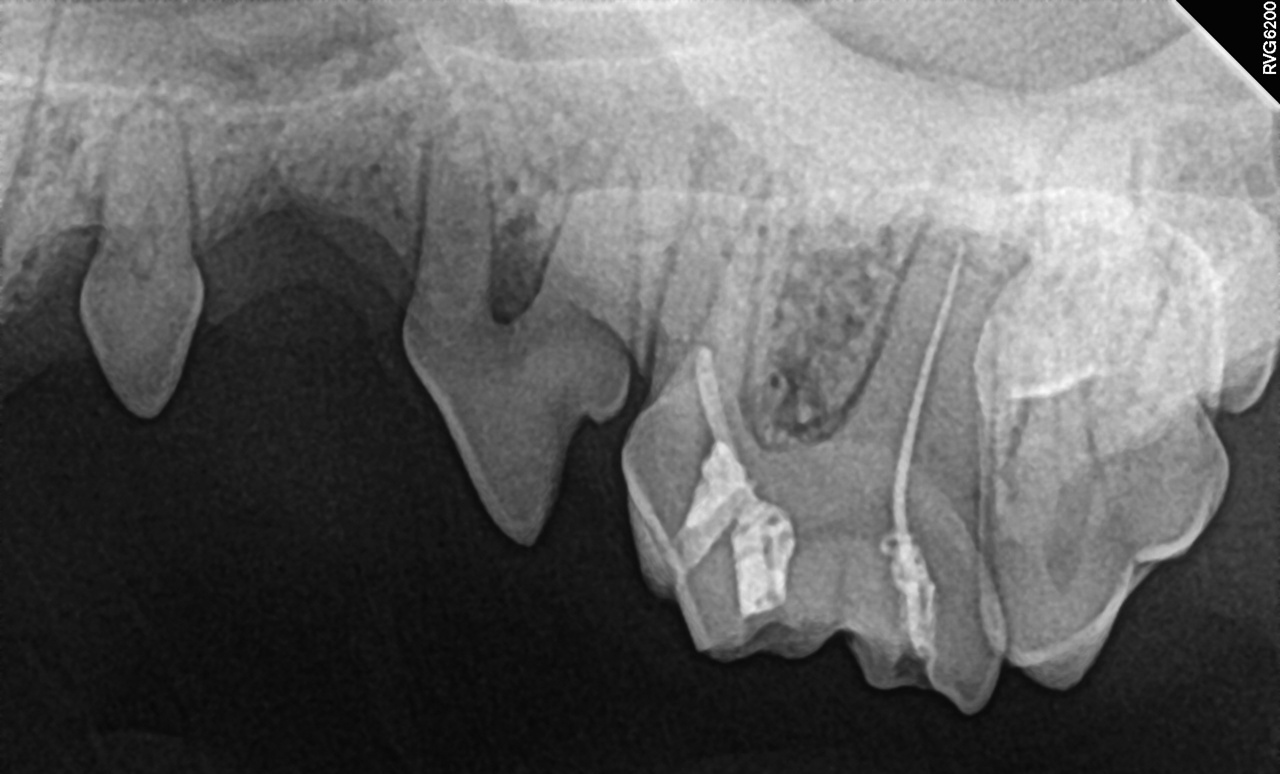

현재 수의치과학에서의 근관치료는 사람의 근관치료를 위해 개발되고 발전해 온 기구와 재료를 사용할 수밖에 없는 현실에 놓여 있다. 그러나 사람과 개, 고양이의 근관 해부학적 특성은 분명히 다르다. 따라서 이러한 기구와 재료를 개와 고양이의 근관 해부학에 맞게 적절히 변형(modification)하여 적용하는 것이 중요하다. 특히 사람에 비해 훨씬 복잡한 apical delta가 발달한 개와 고양이에서는 근단 1/3 부위를 얼마나 효과적으로 성형·세정·충전하는지가 높은 성공률을 좌우한다는 점이 최근 발표된 여러 문헌을 통해 확인되고 있다.

과연 근관치료의 원칙에 맞게 치료 과정이 수행되고 있는지, 그리고 그 결과를 영상학적으로 확인하고 있는지, 더 나아가 술후 일정 시간이 지난 뒤에도 이를 다시 평가하고 있는지 말이다. 혹시 올바르게 수행되지 않은 근관치료의 본질은 외면한 채, 눈으로 확인되는 치관 수복의 외형만으로 치료 결과를 논하고 있지는 않은지 스스로에게 질문해 볼 필요가 있다.

우리의 환자는 말이 없다. 고통과 불편함을 스스로 표현하지 못한다. 그렇기에 원칙에 충실한 치료와 객관적인 영상학적 검증은 선택이 아니라 필수이다. 근관치료는 술식이 끝나는 순간 종료되는 행위가 아니다.